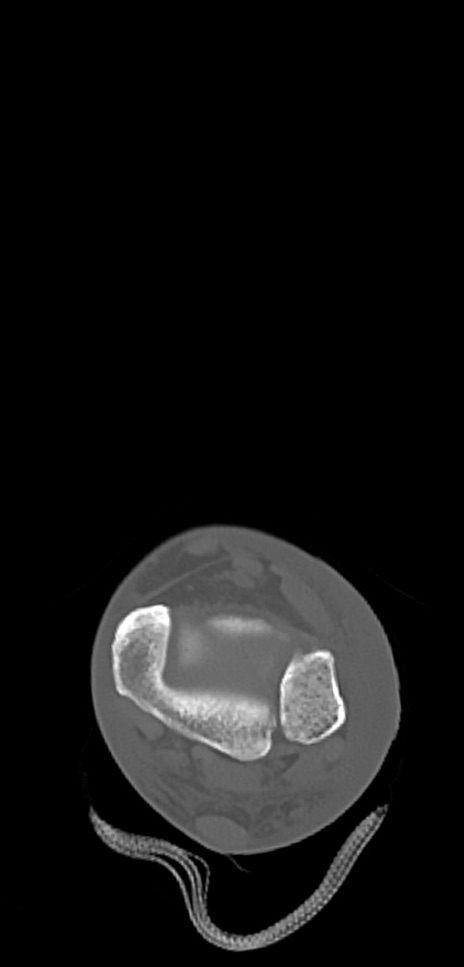

症例37 左足関節CT(横断像)

左足関節CT